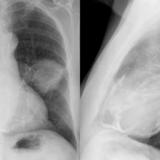

Peric stripe - slightly thickened

close up